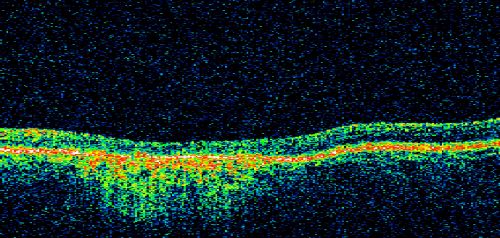

Stargardt's Disease - Macular Dystrophy - 69 Year Old African American Male - 20/200 both eyes

69-year-old man has had vision loss in both eyes starting 20 years ago. He was diagnosed at one point with Stargardt’s macular dystrophy.  When I saw him, he had retinal atrophy in each eye.

Vision is 20/200 in each eye